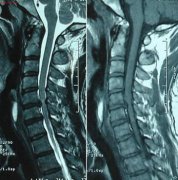

现如今我们都知道强直性脊柱炎是属于骨科疾病之一,但是多数人对 ...

强直性脊柱炎是骨科较常见的一种疾病,所以对治疗时会带来一些不 ...